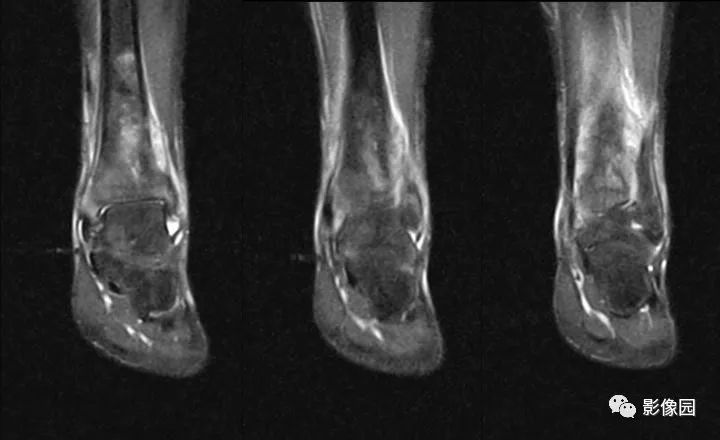

评论:前片X线示左胫骨下段及干骺端病变,髓腔内密度不均匀增高,内侧骨皮质可见骨质破坏,可见骨膜反应。CT示病灶内见多发斑片状肿瘤骨(黄色箭头),周围可见针状骨膜反应(红色箭头)。周围软组织肿胀。MRI示胫骨下段以长T1、长2信号为主的混杂信号影,未跨越胫距关节面,周围未见明显软组织肿块。周围软组织广泛片状长T1长T2信号影。复查X线示病变较前片明显进展,左侧胫骨远段及干骺端骨质破坏,周围可见针状骨膜反应及Codman三角(蓝色箭头)形成。相邻左侧腓骨下端、距骨滑车受累。